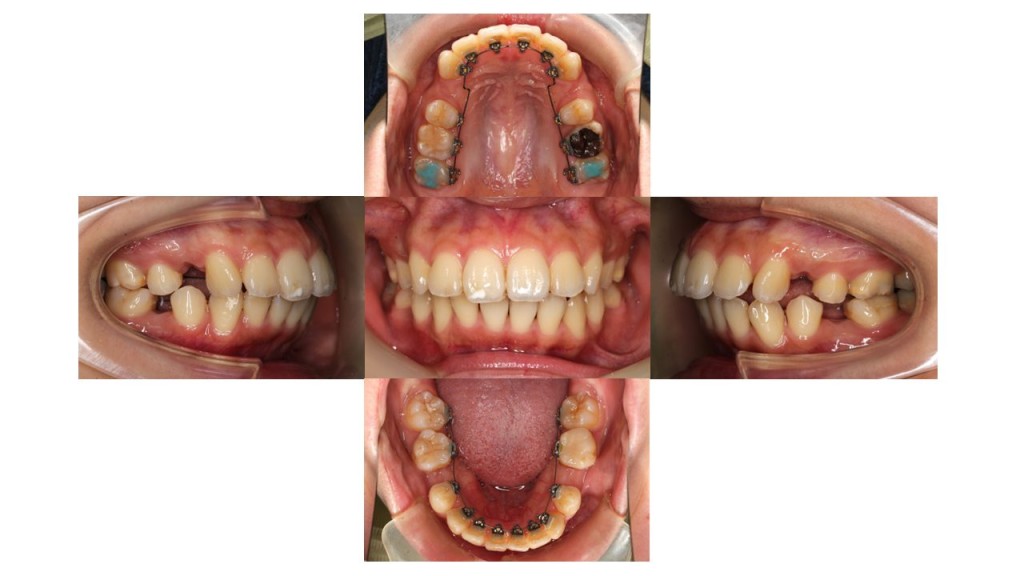

上下ともに裏側の装置で動かし、2カ月経過の口腔内の状態です。

特に下の前歯の凸凹が少しずつ改善してきました。